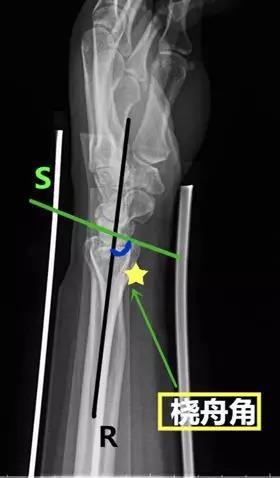

- 桡舟角:在腕关节侧位片桡骨与舟骨(掌侧与背侧)中轴线的夹角。

- 正常值:55°~75°

- 临床意义:>75°提示腕关节不稳。